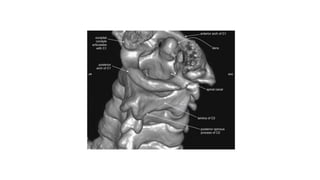

This three-dimensional CT model is oriented with the observer looking cephalad along the anterior

surface of the cervical spine. A series of holes perforating the transverse processes of each vertebra

can be seen—the transverse foramen.

This three-dimensional CTmodel is oriented with the observer looking cephalad along the anterior surface of the cervical spine. A series of holes perforating the transverse processes of each vertebra can be seen—the transverse foramen.